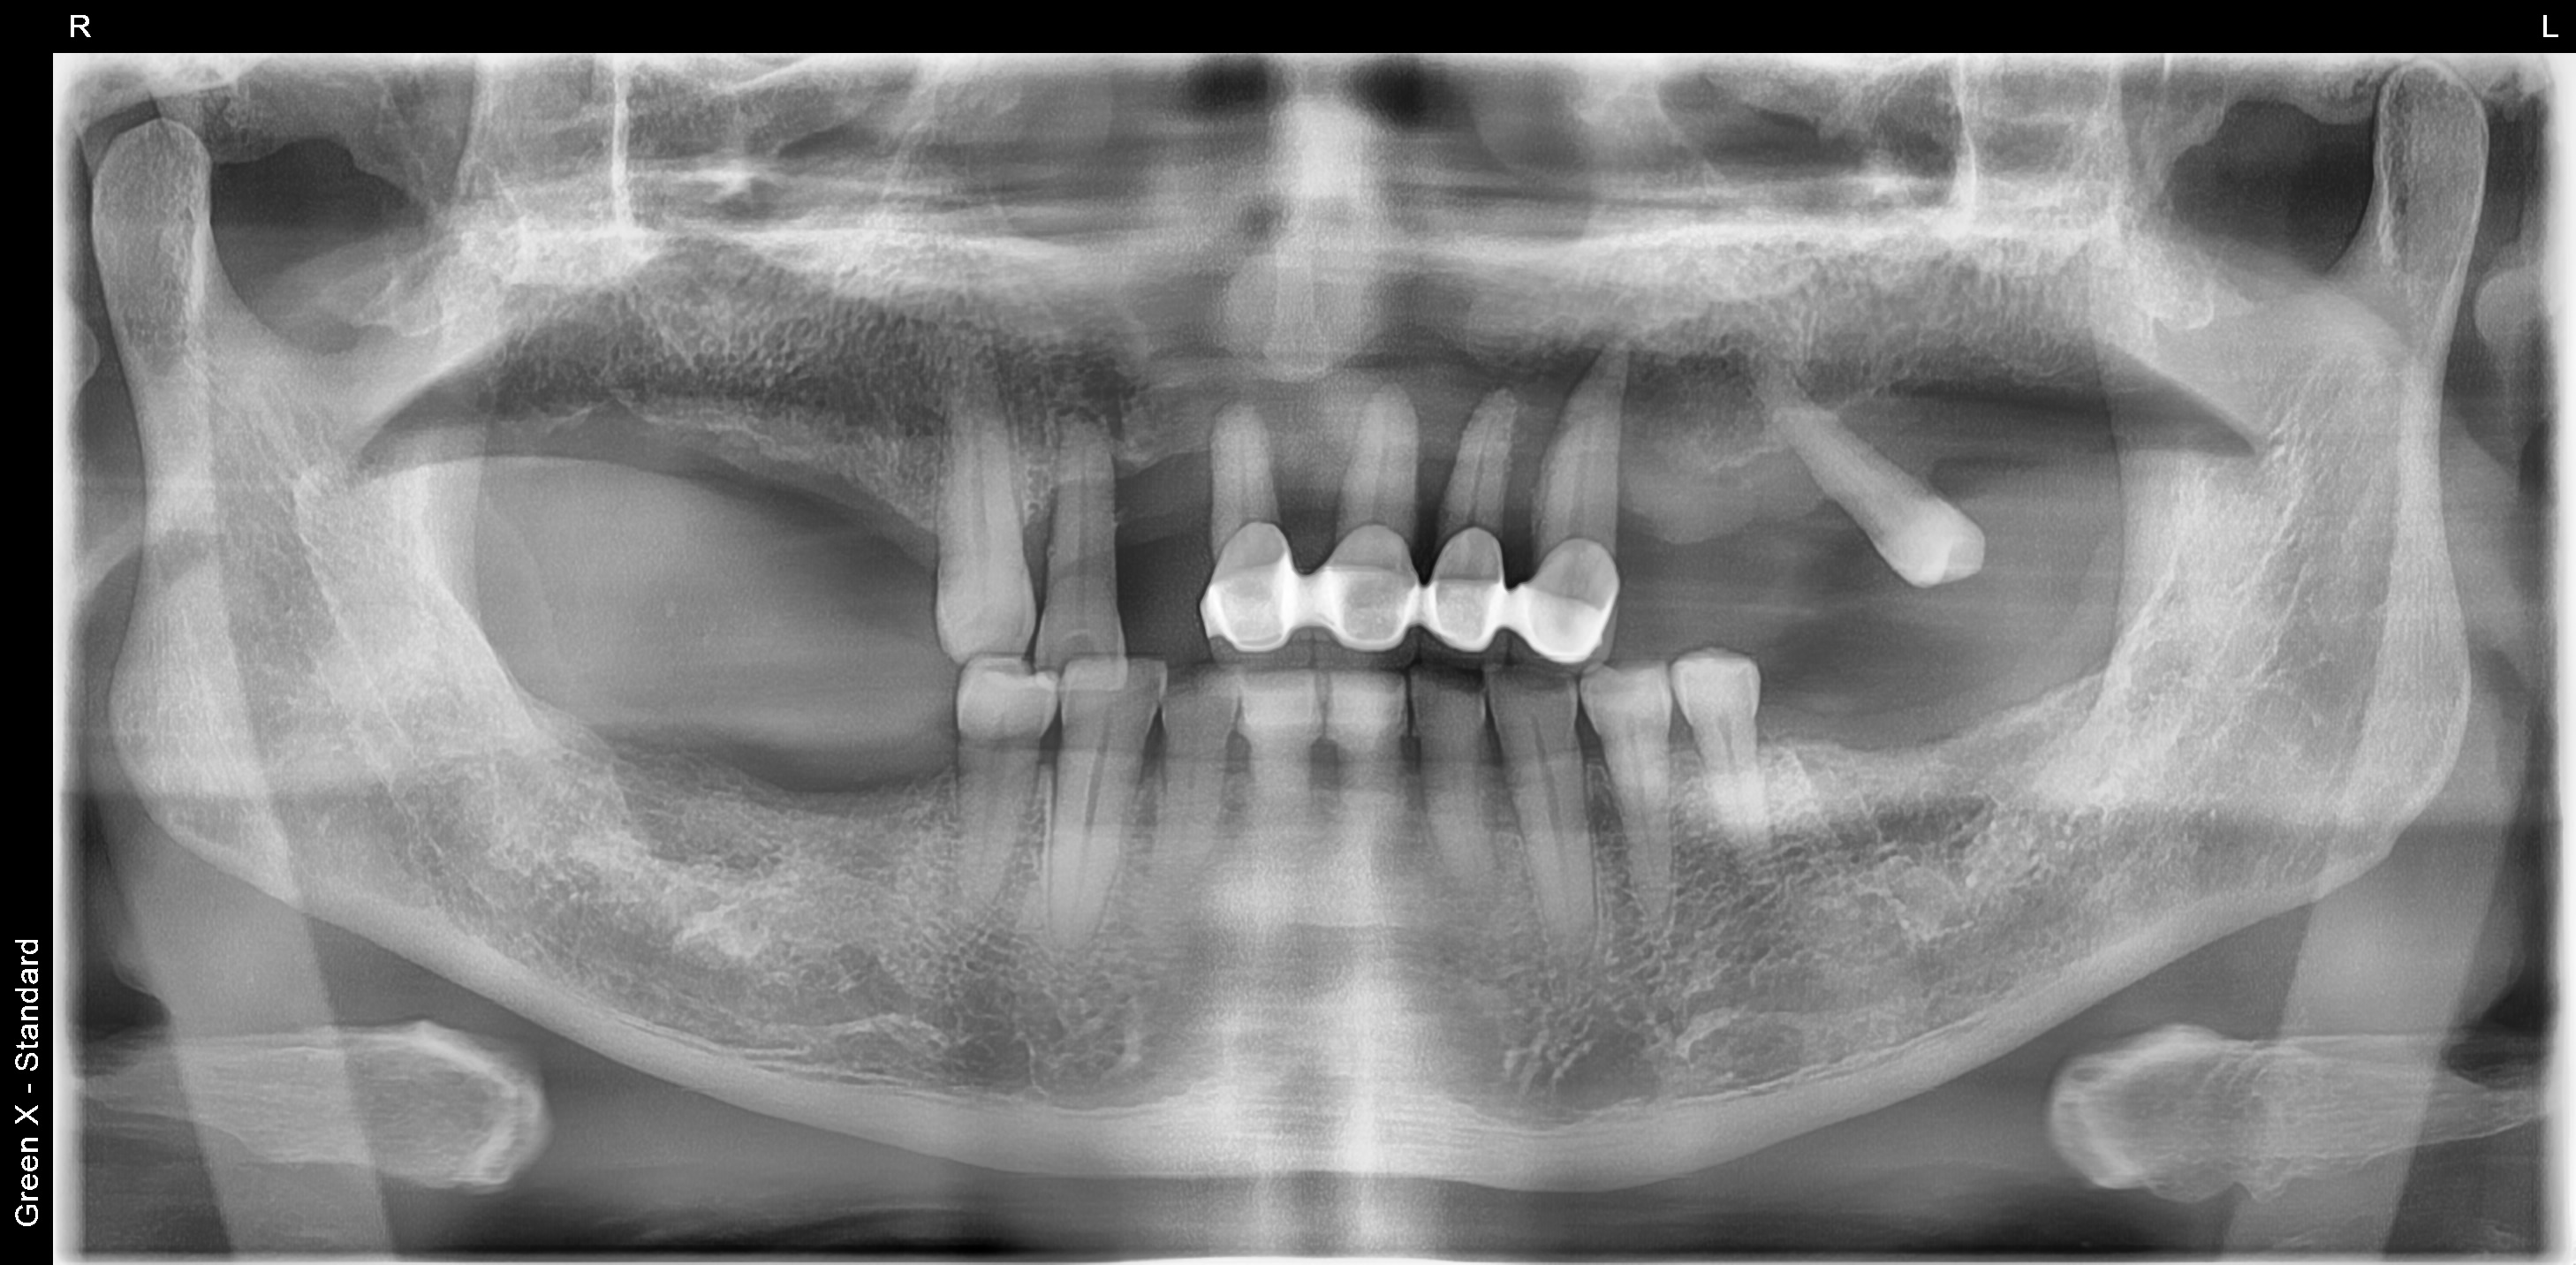

오랜기간 어금니가 없이 지내셨던 60대 남성분의 치료 사례입니다.

처음 김포 치과에 내원하셨을 당시 위에는 송곳니 하나를 제외하고는 다 흔들리고 어금니는 빠진지 오랜된 상태였습니다.

<치료 전>